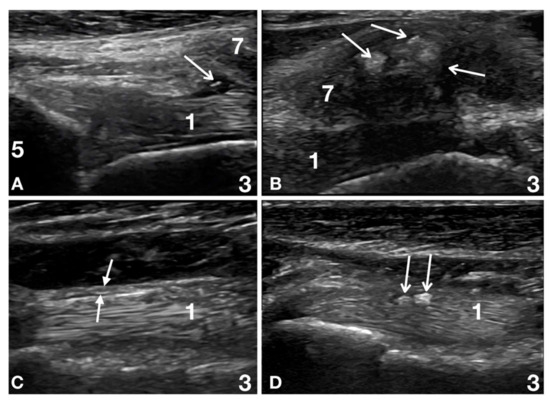

2.3. Ultrasound Evaluation